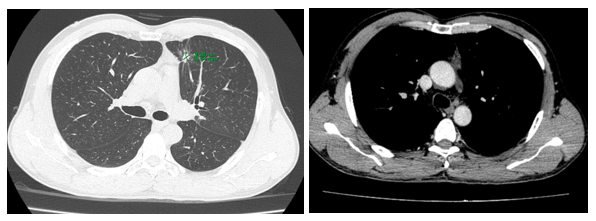

- CT ổ bụng:

Hình 3. Trên phim chụp CT ổ bụng: Nhu mô gan sát bao gan phân thùy S5 có nốt giảm tỷ trọng trước tiêm, ngấm thuốc kém sau tiêm, đường kính 10mm – Theo dõi tổn thương thứ phát. Dày tuyến thượng thận trái.

Trên phim chụp cắt lớp vi tính ổ bụng:

Trước điều trị:

Sau 3 tháng điều trị: Tổn thương gan và thượng thận đã biến mất.

Hiện tại trong quá trình theo dõi gan và thượng thận 2 bên vẫn chưa xuất hiện tổn thương mới.